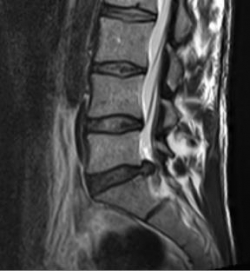

MRI with lateral reconstruction of the lumbar spine. In the area of the lowest intervertebral disc, a protrusion of the intervertebral disc to the right (back) can be seen

In the case of a herniated disc, the disc nucleus emerges through the ruptured disc ring. If this gelatinous core shifts backwards into the spinal canal, the nerve root located there may be displaced. The affected person feels this pressure as pain in the nerve supply area. For example, there may be pain in the buttocks or calf (herniated disc in the lumbar spine) or pain or tingling in the arm or fingers (herniated disc in the cervical spine). Most herniated discs can be treated without surgery. As a rule, the symptoms are almost completely gone after 12 weeks at the latest. However, if there is no pain relief after several months despite good conservative therapy, microsurgical removal of the herniated disc can bring about rapid relief of symptoms.